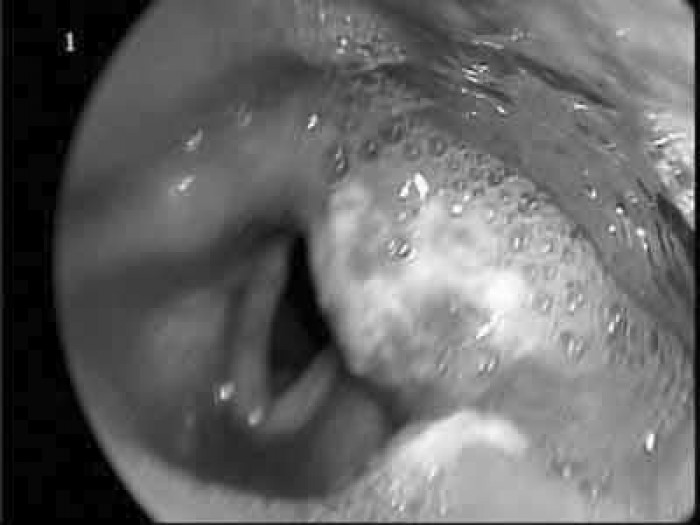

2. Nghẹt mũi

| Nghẹt mũi là một dấu hiệu của bệnh |

Sau khi xuất hiện khối u, sẽ có hiện tượng tắc 1 bên mũi, khi khối u to lên sẽ khiến 2 bên đều bị nghẹt.